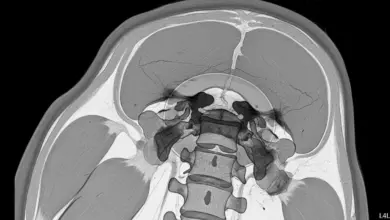

Escoliose é uma alteração tridimensional da coluna. Não é só “entortar” para o lado.

As vértebras também giram, o que muda o alinhamento do tronco e pode aparecer como assimetria de ombros, cintura ou costelas.

O risco mais discutido é o respiratório, pois curvas torácicas muito grandes podem reduzir a expansibilidade do tórax e diminuir a eficiência ventilatória.

Em escolioses muito graves, com ângulos altos e rotação importante, pode haver restrição pulmonar, cansaço aos esforços e piora progressiva da tolerância a atividades.